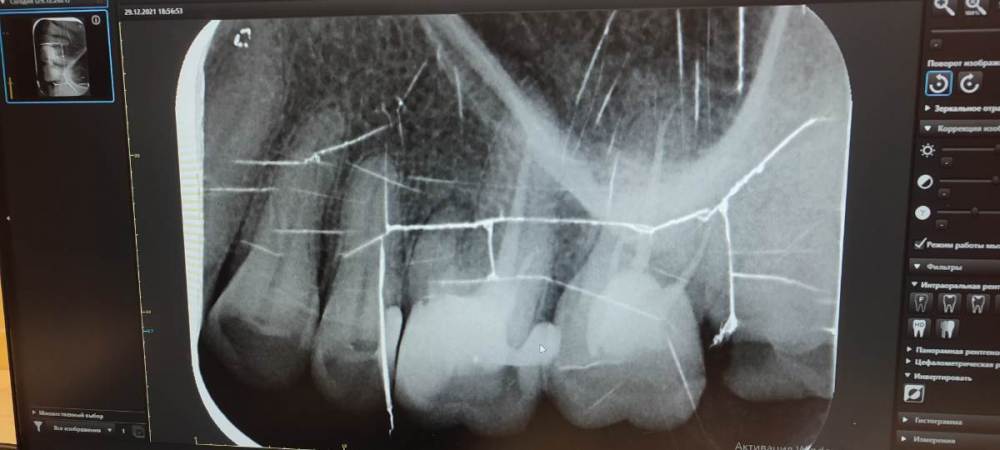

Люлякебаб Опубликовано 30 декабря, 2021 Поделиться Опубликовано 30 декабря, 2021 Здравствуйте, уважаемые специалисты! Зуб шестёрка верхняя. Были прочищены каналы. Поставлена пломба. Лет 10 назад. Сколько-то лет назад на десне в районе зуба появился бугорок в диаметре около 5 мм. В последнее время зуб реагирует на горячее и холодное. Иногда болит, но проходит. По снимку врач увидела, что не всё каналы прочищались. Советует найти специалиста по прочистке каналов под микроскопом. Другая врач общей практики считает разумным только удаление и последующую имплантацию. Я в замешательстве. Первый вариант невероятно дорог. Второй рискован, впрочем, как и первый. Что делать? Ещё между пятёркой и шестёркой этой я зубочисткой нащупываю неровности с резкой болью и запах (извините за подробности). Ссылка на комментарий

It'sGeorgy Опубликовано 18 января, 2022 Поделиться Опубликовано 18 января, 2022 (изменено) Добрый день. 30.12.2021 в 20:32, Люлякебаб сказал: Что делать? Начните с КТ. И для диагностики, и для возможного перелечивания, и для возможной имплантации вам она все равно потребуется. 30.12.2021 в 20:32, Люлякебаб сказал: Ещё между пятёркой и шестёркой этой я зубочисткой нащупываю неровности с резкой болью и запах (извините за подробности). Судя по предоставленному снимку с пятеркой тоже могут быть проблемы. Не исключено, что беспокоит вас именно она. Изменено 18 января, 2022 пользователем It'sGeorgy 1 Ссылка на комментарий

dentikl Опубликовано 18 января, 2022 Поделиться Опубликовано 18 января, 2022 снимок тертый,но мне видится выпавшая пломба в 8 1 Ссылка на комментарий

Irouil Опубликовано 19 января, 2022 Поделиться Опубликовано 19 января, 2022 Сделайте КТ, будет больше пищи для обсуждения пока что те жалобы, что Вы предъявляете, более характерны для живых зубов, а таких подозреваемых 2 - соседняя 5-ка и 8-ка 1 Ссылка на комментарий